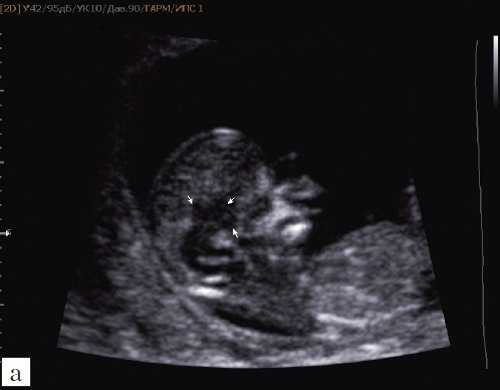

При изучении стандартных ультразвуковых сканов (рис. 6-8) было подтверждено наличие синдрома Арнольда-Киари, вентрикуломегалии, открытой расщелины позвоночника - рахисхиза без кистозного компонента в поясничном отделе у плода в 12,4 недель беременности.

Рис. 6. Проявление синдрома Арнольда-Киари - смещение мозжечка, признак "банана" у плода со spina bifida, беременность 12,4 недель.